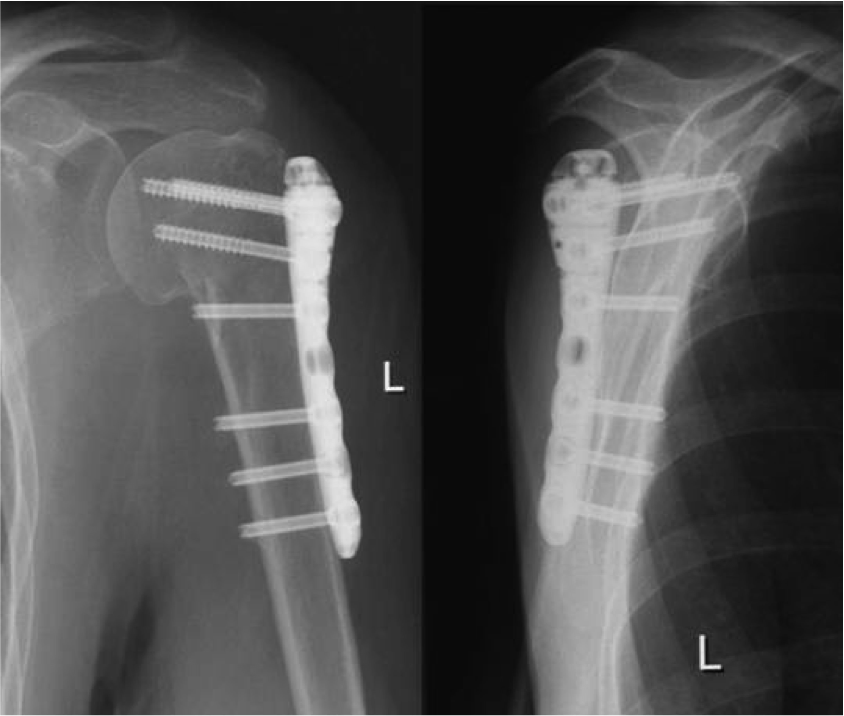

Медицинские снимки: Пластина в левом предплечье